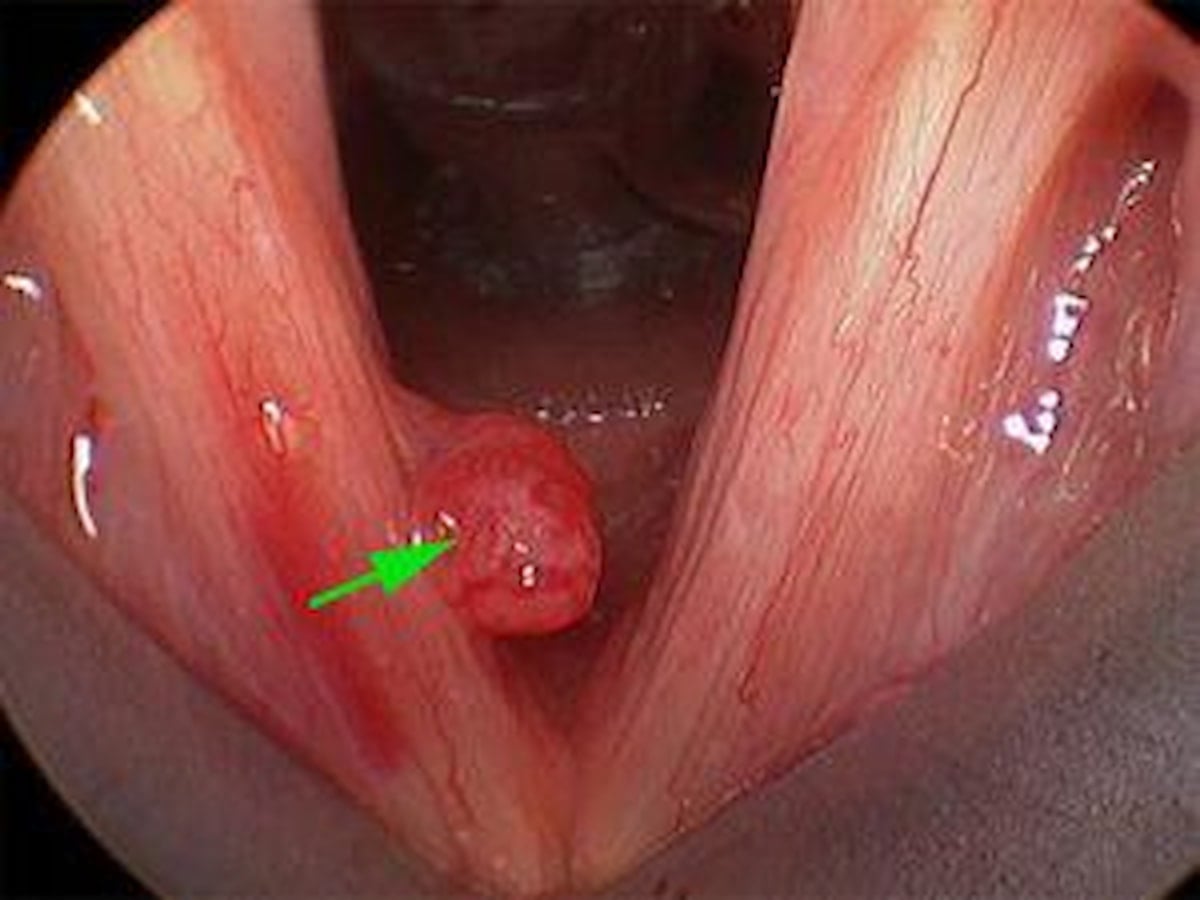

Sesin doğru kullanılmaması sonucu ses tellerinde bozulma meydana gelebilir, bu nedenle de nodüller oluşur.

Nodüllü ses teli görüntüsü: